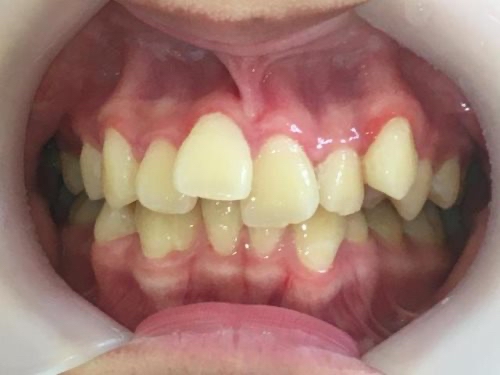

叢生(そうせい)

叢生(そうせい)とはいわゆるガタガタの歯並びのことを指します。

満員電車を想像してみてください。たくさんの人がいる窮屈な電車の中で、少しのスペースに不自然な体制で人が密集していますよね。歯並びも同じです。十分なスペースがない歯茎に無理やり歯が生えている状態、それが叢生です。